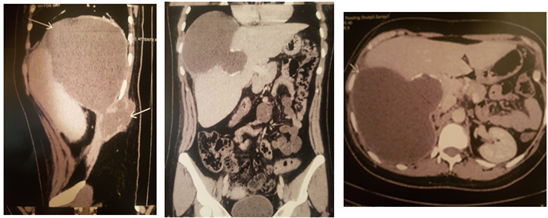

The chest x-ray did not show any obvious lesion. Abdominal computed tomography (Figure 1) showed a cystic lesion of the liver coming into contact with the right lateral thoracic wall,

Figure 1. A computed tomography scan (CT) revealed a large cystic liver lesion interesting the right liver extending to involve right lateral chest wall forming a collection in an intermuscular.